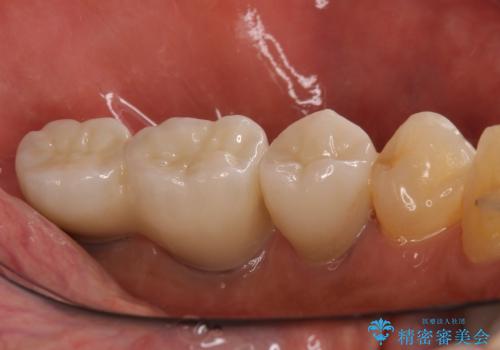

追加のインプラントと、歯肉移植による磨きやすい歯肉に改善

インプラント埋入後、手前のインプラント周りの丈夫な歯肉(角化歯肉)が失われてしまったため、角化歯肉の移植を行うこととなりました。

十分な角化歯肉が獲得でき、清掃性の高い環境が達成されました。